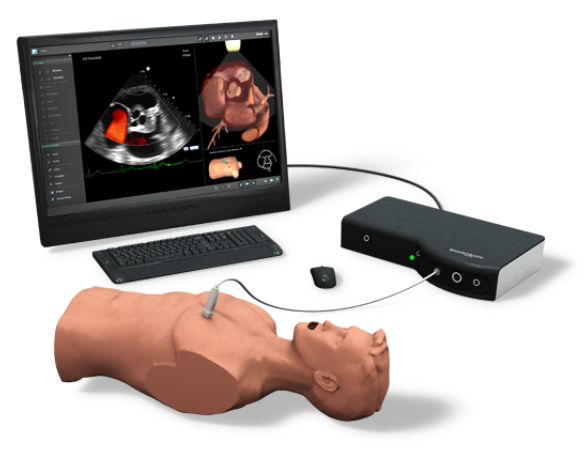

Simbionix U/S Mentor

Ultrasound & Echocardiograhy Virtual Reality Simulator

U/S Mentor - Ultrasound & Echocardiograhy Simulator from Simbionix

SIMBIONIX U/S MENTOR:

The Simbionix U/S Mentor is a multidisciplinary simulator that will offer hands-on training for diverse ultrasound examinations and interventions, as performed by a rapidly growing number of medical specialties.

The U/S Mentor features a highly realistic simulation within a comprehensive educational environment, supporting independent or instructed hands on training.

The simulation environment combines high level of realism with advanced educational aids, featuring:

- A reliable ultrasound display of anatomy per probe position, incorporating common ultrasound imaging attributes and artefacts.

- Realistic setup with palpable mannequin and true to life anatomies physiology and pathologies.

- Incorporated image enhancement tools, measurement tools, color Doppler, cine-loops recording and clinical findings reporting support training to the full extent of the actual procedure.

- Various educational aids such as anatomy labels, corresponding external visualization, standard views helpers and more are available to accelerate the learning curve and support independent training.

- Didactic materials enhancing procedural and clinical understanding.

- Unique training modes such as Instructional Mode and Procedure Restricted Mode (no helpers available) complement the Normal training mode.

- Captured performance objectives provide self assessment opportunity, as well as competency level monitoring by an instructor.